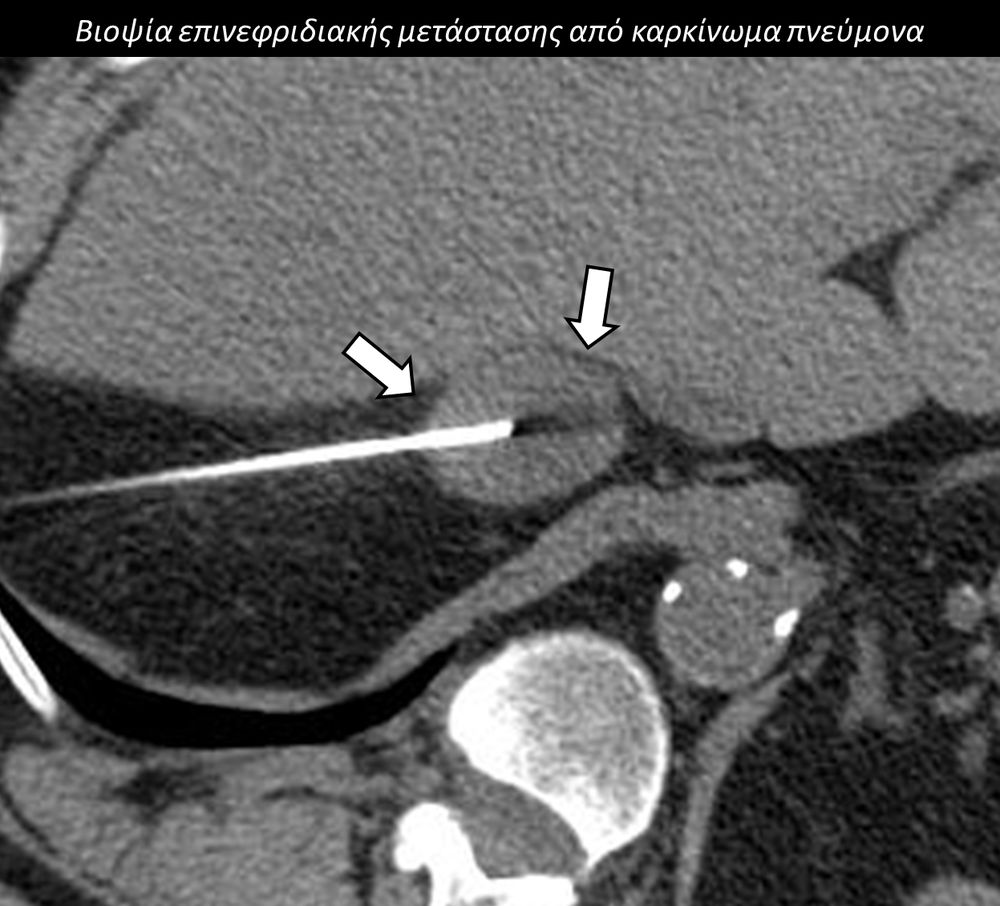

Η διαδερμική βιοψία είναι μία ελάχιστα επεμβατική μέθοδος λήψης υλικού από τον όγκο για κυτταρολογική και ιστολογική εξέταση, από εστιακές αλλοιώσεις του ήπατος, πνεύμονα, νεφρού κλπ. Συστήνεται από τον κλινικό ιατρό ανάλογα με το είδος και το μέγεθος της βλάβης και πραγματοποιείται με ασφάλεια από επεμβατικό ακτινολόγο με την καθοδήγηση αξονικού τομογράφου ή υπερήχων. Στη σύγχρονη ογκολογική θεραπεία όπου γίνεται προσπάθεια καταπολέμησης του καρκίνου σε μοριακό επίπεδο κρίνεται αναγκαία η ακριβής ιστολογική ταυτοποίηση του όγκου ώστε να εφαρμοσθεί εξατομικευμένη θεραπεία για το βέλτιστο αποτέλεσμα. Οι κατευθυνόμενες βιοψίες στοχευουν στο να παρέχουν στον κλινικό ογκολόγο το απαραίτο ιστοπαθολογικό υλικό που θα του επιτρέψει να εφαρμόσει την κατάλληλη θεραπεία για τον ογκολογικό ασθενή.